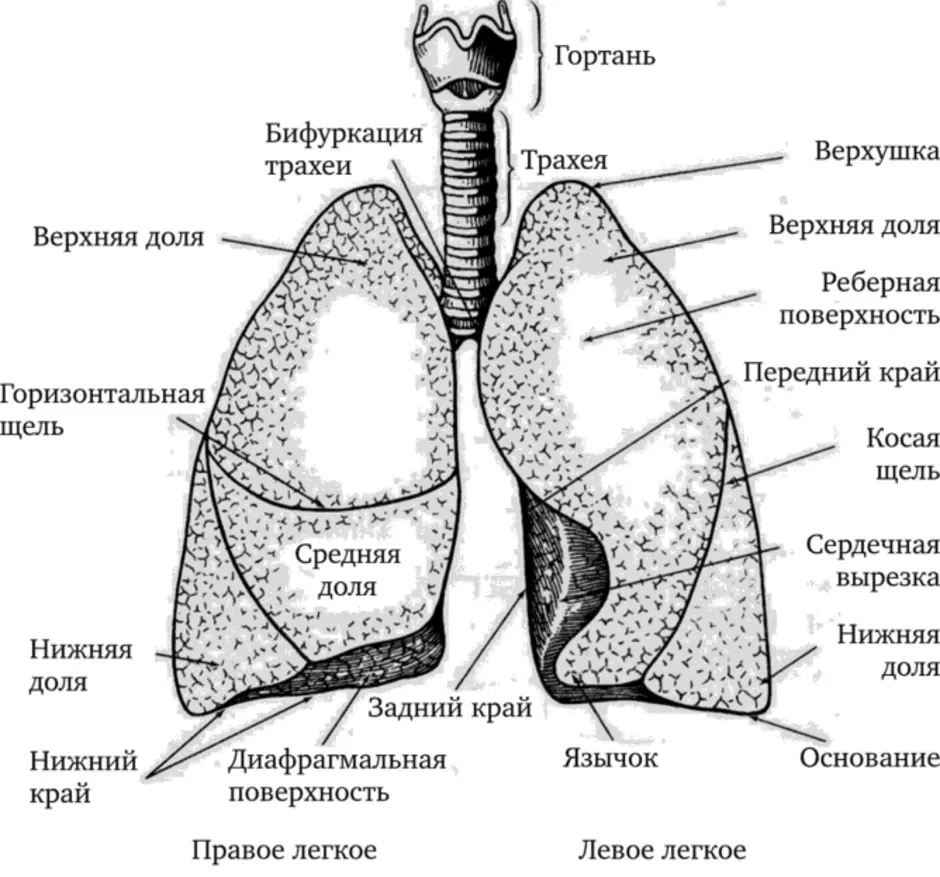

Таинство дыхания: глубокий взгляд на легкие человека в картинках

Раздел: Снимки-откровения